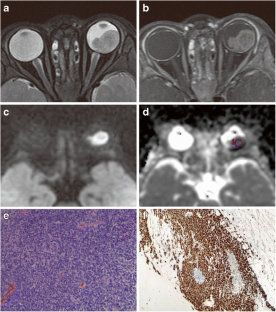

Fig. 2